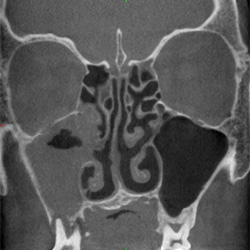

• Chronische Nasennebenhöhlenentzündungen

• Häufig wiederkehrende Nasennebenhöhlenentzündungen

• Polypen der Nasenhaupthöhle

Chronisch polypöse Pansinusitis linksMukozele im linken Siebbein

mit Unterbrechung der Frontobasis

Z.n. Pansinus-Operation